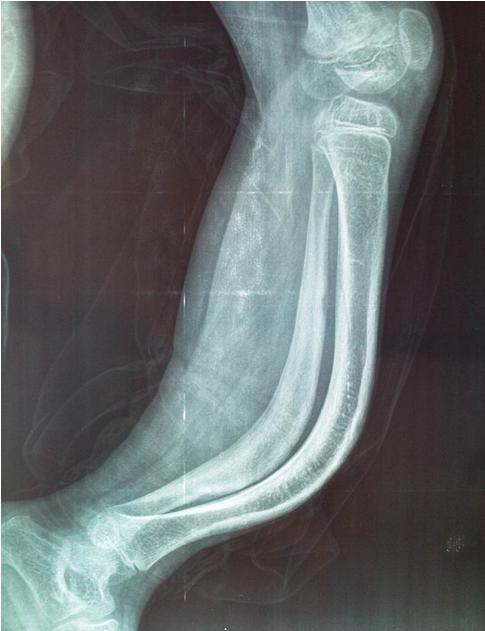

那什么是“青枝骨折”呢,这样说吧,小儿的骨头韧性强,强度小,容易发生变形,一旦发生骨折,常会出现“折而不断”的现象,这就是“青枝骨折”:仅有部分骨质和骨膜被拉长、皱褶或破裂,常有成角、弯曲畸形,如清嫩的树枝被折断状的一类骨折,多见于儿童。单纯的青枝骨折均无需固定,上肢适度制动即可。如果是完全断裂就不叫青枝骨折了,8岁以下的孩子如果锁骨青枝骨折通常都采用8字绷带固定,上肢悬吊。大龄孩子甚至成人就要看骨折对位对线情况再决定是否是保守治疗还是手术治疗了。

大家猜猜这个图是青枝骨折吗?